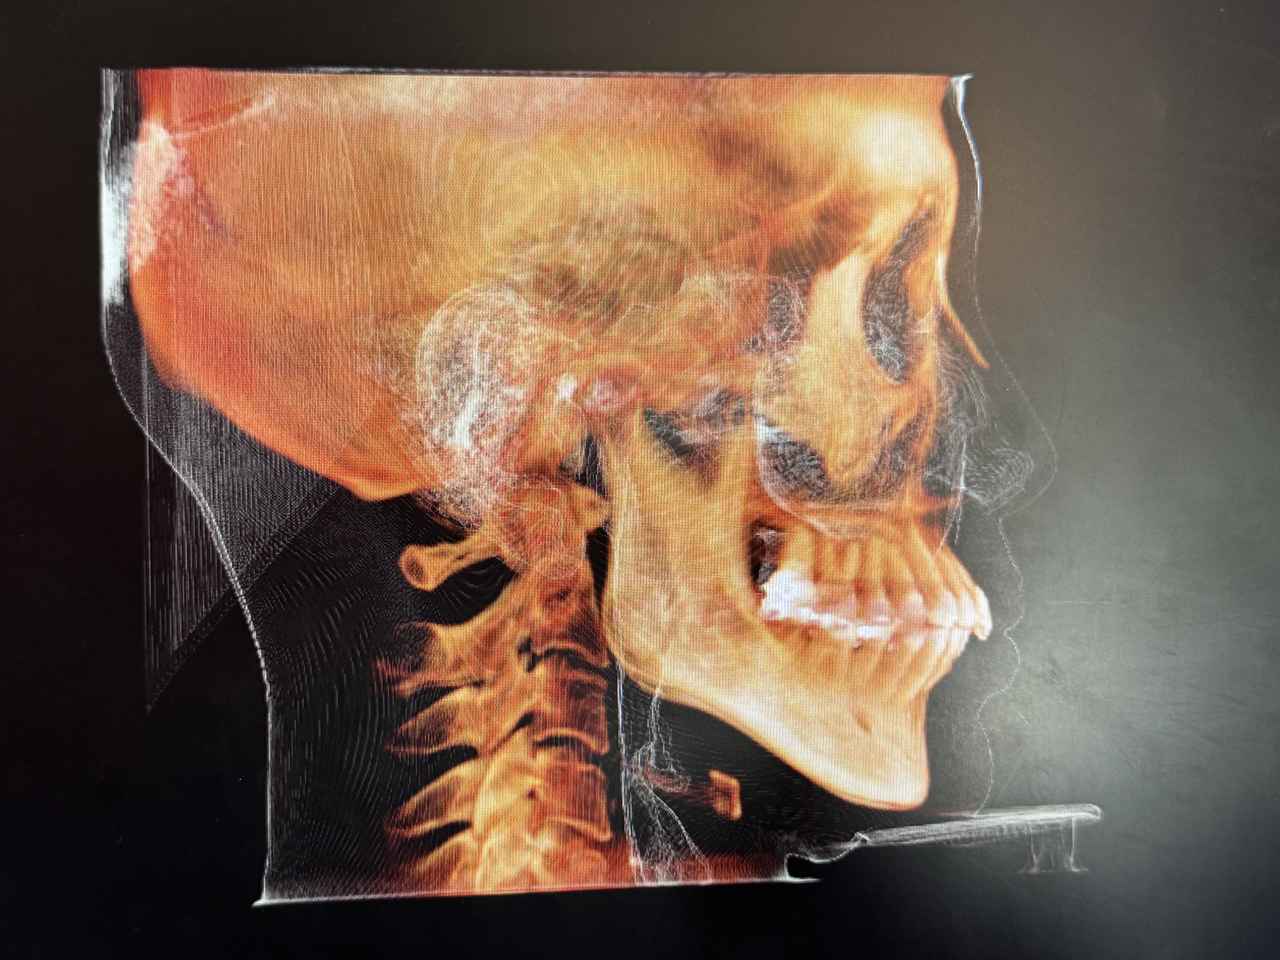

強い奥歯の噛みしめで頭蓋骨にまで影響がでていることが判明

気道が狭くなっているのまでわかります。

鼻の周りが詰まっているとのこと。鼻づまりなんて体験なかったのでショックでした。

歯科用CTは、顎の骨や歯の位置を立体的に捉えることができるため、従来のレントゲンでは見えにくかった細部まで確認することができます。特に「こどもと女性の歯科クリニック」では、かみ合わせの診断に加えて、今回は、以下のような項目もチェックしてくれました。

頭位や頸椎の傾き:

姿勢のクセや左右差が、顎の位置やかみ合わせに影響していることがあります。

呼吸の通り道(気道):

気道が狭くなっていると、口呼吸や睡眠の質に影響する可能性があります。

顎関節の状態:

顎の動きや関節の形状から、食いしばりや顎関節症のリスクを確認できます。

骨格のバランス:

顔の左右差や骨の成長具合など、全身の姿勢にも関係する情報が得られます。

姿勢と口腔の関係は、想像以上に深い

姿勢が悪いと、顎が後方に下がり、かみ合わせがズレたり、気道が狭くなったりすることがあります。その結果、口呼吸になりやすくなったり、歯並びに影響が出たりすることも。歯科用CTは、こうした“見えない原因”を可視化することで、より根本的な治療や予防につなげることができます。歯のことだけでなく、姿勢や呼吸まで見てもらえるなんて驚きでした。